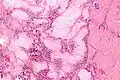

Gross pathology of a large tophus -

Micrograph of a gouty tophus -